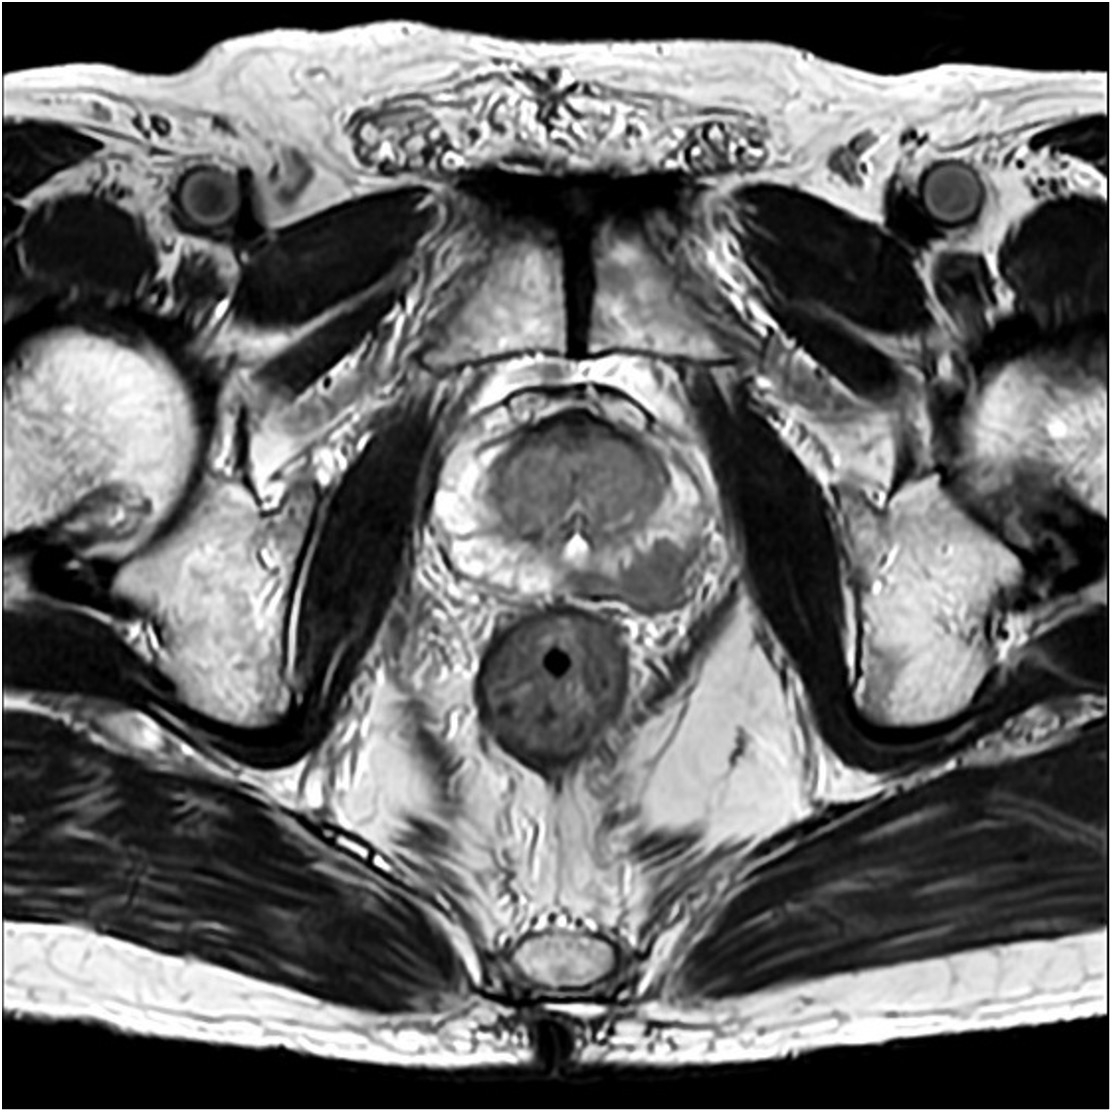

当院では、2008年から前立腺針生検前にはMRI(造影剤を使わない単純撮影)を行っております。これまでに当院放射線科では、2000例以上の前立腺MRI検査実施経験から、細かい撮影条件設定を行い、よりS/N比の高い画像を得るための努力を続けてきております。下に示す画像(Fig.1)は、最近の3T-MRIでの代表的前立腺癌症例ですが、前立腺左葉辺縁域にはっきりと撮影されている癌病巣がわかると思います。PSA二次検診の方法には施設によってさまざまですが、現在では前立腺癌診断には、このMRIで得られる画像所見こそが、最も客観的かつ診断に寄与する、と考えております。当院の画像をぜひご覧ください。

現在まで、当院のPSA二次検診では、できるだけお待たせしないように3T・MRI検査を実施し、癌が想定される部位をあらかじめ確認して、その所見部位を正確に生検するという、標的生検法を行っております(経会陰式)。こうした画像をもとに前立腺生検を行うとすれば、例えば1本でも正確に採取できれば癌診断ができると考えております(実際には標的部位本数+6本程度)。二次検診MRIで癌を疑う所見がないとすれば、前立腺肥大症か前立腺炎と考えられますので、排尿症状などに応じて適切に内服治療し、経過観察ができれば、迅速な針生検検査は避けてよい、と考えています。

実際の当院での前立腺標的生検法は、当院で実施している前立腺癌根治放射線治療の1つ、密封小線源治療の技術(過去750例実施)を応用し、感染症合併が少なく、直腸出血も少ない経会陰式で行っております。入院で、腰椎麻酔で実施しておりますが、最近の4年間の前立腺針生検を実施した場合の癌検出率は下表に示しております(Table 1)。生検を受けられた患者様の約80%以上に前立腺癌が検出されていますが、その多くはMRI標的部位から検出されています。診断後は、骨シンチ検査など追加画像診断を実施し、診断時PSA値。病理組織所見、画像診断から米国のNCCN分類にわけて治療法を説明しております。患者様の状態、希望に合わせた最適な治療法を、放射線治療中心にご案内しております。さらに、生検前のMRI画像で癌の局在が治療前にわかっていることも、放射線治療の成績向上に少なからず寄与しております。

Fig.1 MRI